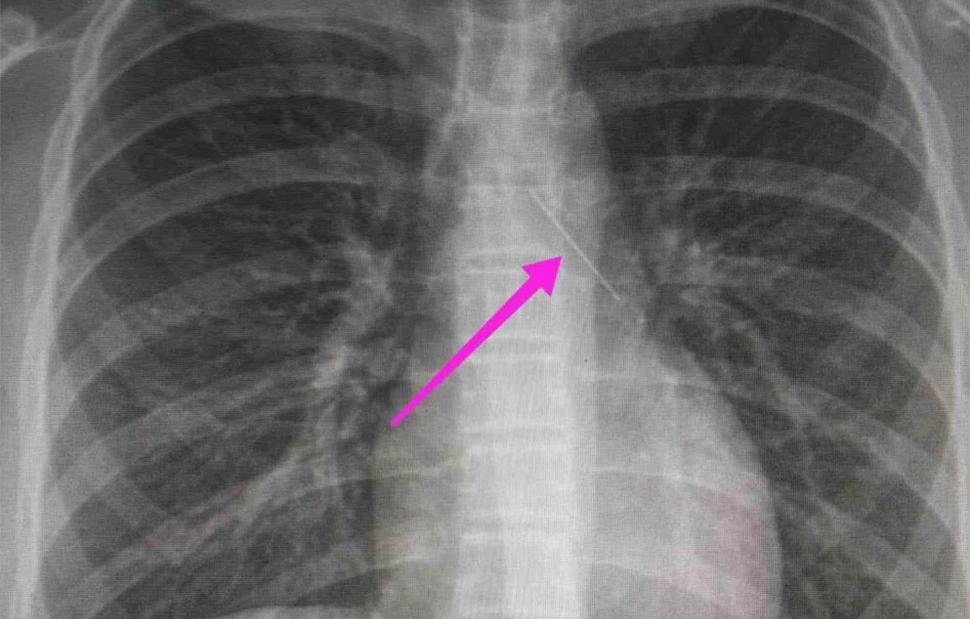

Από την ακτινογραφία θώρακος και την αξονική τομογραφία θώρακος, διαπιστώθηκε «η ύπαρξη αιχμηρού μεταλλικού ξένου σώματος στην αναπνευστική οδό (αριστερός κύριος βρόγχος) και όχι στην πεπτική οδό», αναφέρει η ανακοίνωση του νοσοκομείου, στα μέσα κοινωνικής δικτύωσης, όπου δημοσιεύονται και οι παρακάτω εικόνες.

Η ανήλικη υπεβλήθη σε βρογχοσκόπηση και διαπιστώθηκε η μετακίνηση και ενσφήνωση του αντικειμένου στον δεξιό κύριο βρόγχο. «Μετά οπό εργώδεις προσπάθειες ολοκληρώθηκε με επιτυχία η αφαίρεσή της», δηλώνει το νοσοκομείο.

«Χθες 30/1/2022 στις 16:00 στο Τ.Ε.Π. του ΓΝΘ Ιπποκράτειο, προσήλθε ανήλικη συνοδευόμενη από τους γονείς της, μετά από αναφερόμενη κατάποση ξένου σώματος (καρφίτσα). Από την απεικονιστική διερεύνηση που πραγματοποιήθηκε με ακτινογραφία θώρακος αρχικά και ακολούθως με αξονική τομογραφία θώρακος, διαπιστώθηκε η ύπαρξη αιχμηρού μεταλλικού ξένου σώματος στην αναπνευστική οδό (αριστερός κύριος βρόγχος) και όχι στην πεπτική οδό.

Κατά την βρογχοσκόπηση διαπιστώθηκε η μετακίνηση και ενσφήνωση του ξένου σώματος στον δεξιό κύριο βρόγχο. Μετά από εργώδεις προσπάθειες ολοκληρώθηκε με επιτυχία η αφαίρεση αυτού. Η ασθενής ανένηψε πλήρως εντός της χειρουργικής αίθουσας. Η ασθενής μεταφέρθηκε για παρακολούθηση και νοσηλεία στη Γ’ Παιδιατρική Κλινική.